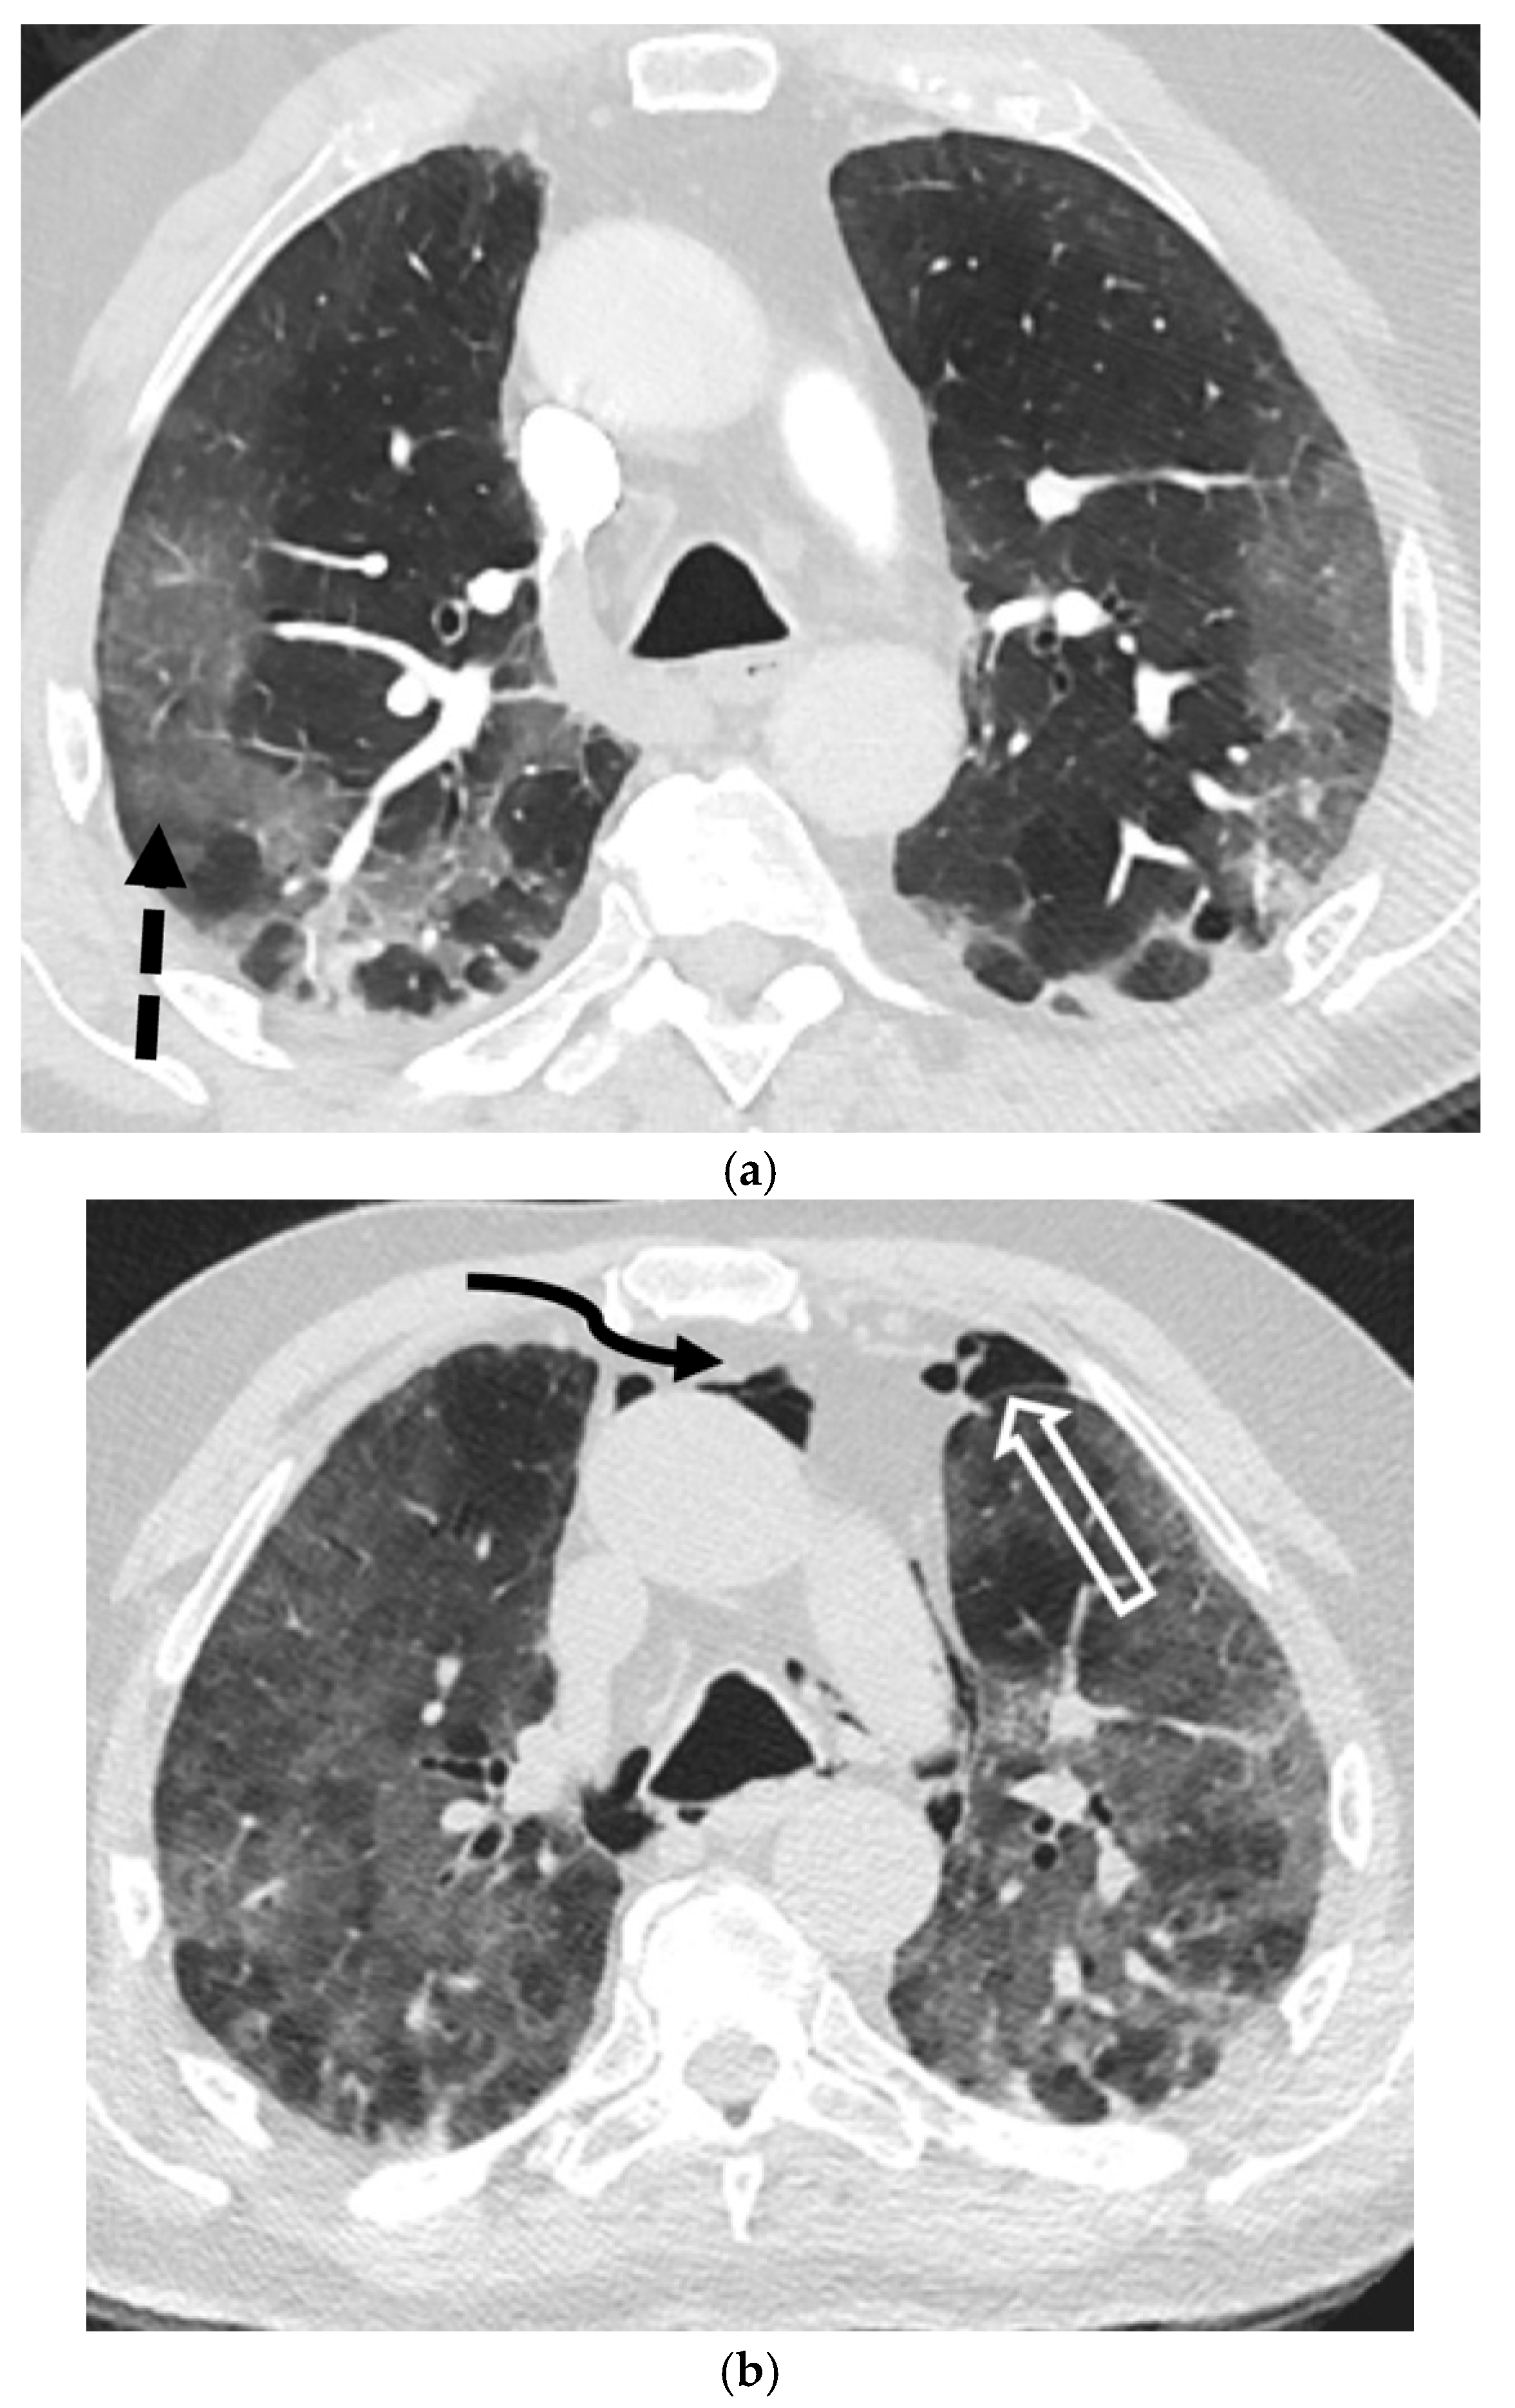

5.1.3. Pneumocystis jirovecii Pneumonia (PJP)

5.1.4. Other Infections